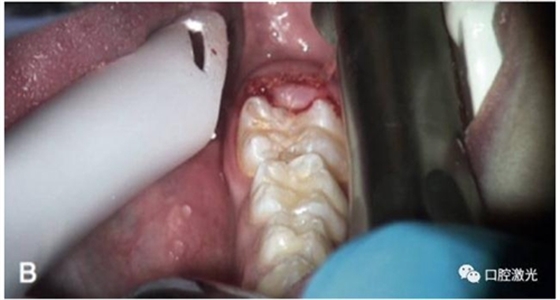

激光盲袋切除術(shù)前

術(shù)中

術(shù)后即刻